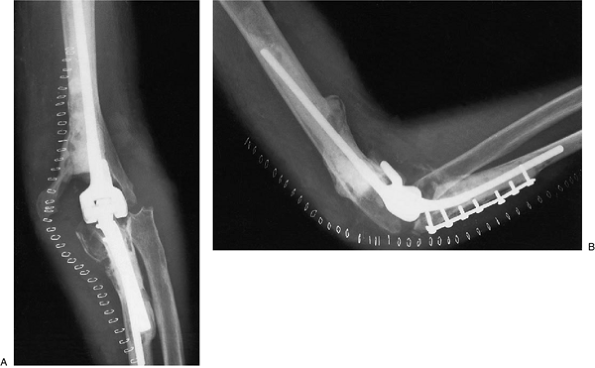

sustained a periprosthetic fracture of the humerus and extensive

erosion of the posterior distal one-third of the humerus (Fig. 19-33).

At surgery the ulnar component was intact. Strut grafts were placed

anterior and posterior, both extending past the fracture (Fig. 19-34). At 1 year the implant is solid, the fracture has healed, and the patient has minimal pain (Fig. 19-35A,B).

Figure 19-34. This was treated by anterior and posterior strut bone graft extending to the level of the articulation.

|

Figure 19-33.

A periprosthetic fracture at the midhumerus associated with grossly loose humeral component and marked distal humeral bone loss. |

![]() |

Figure 19-35. A,B: The fracture has healed and the graft has been incorporated at 1 year.